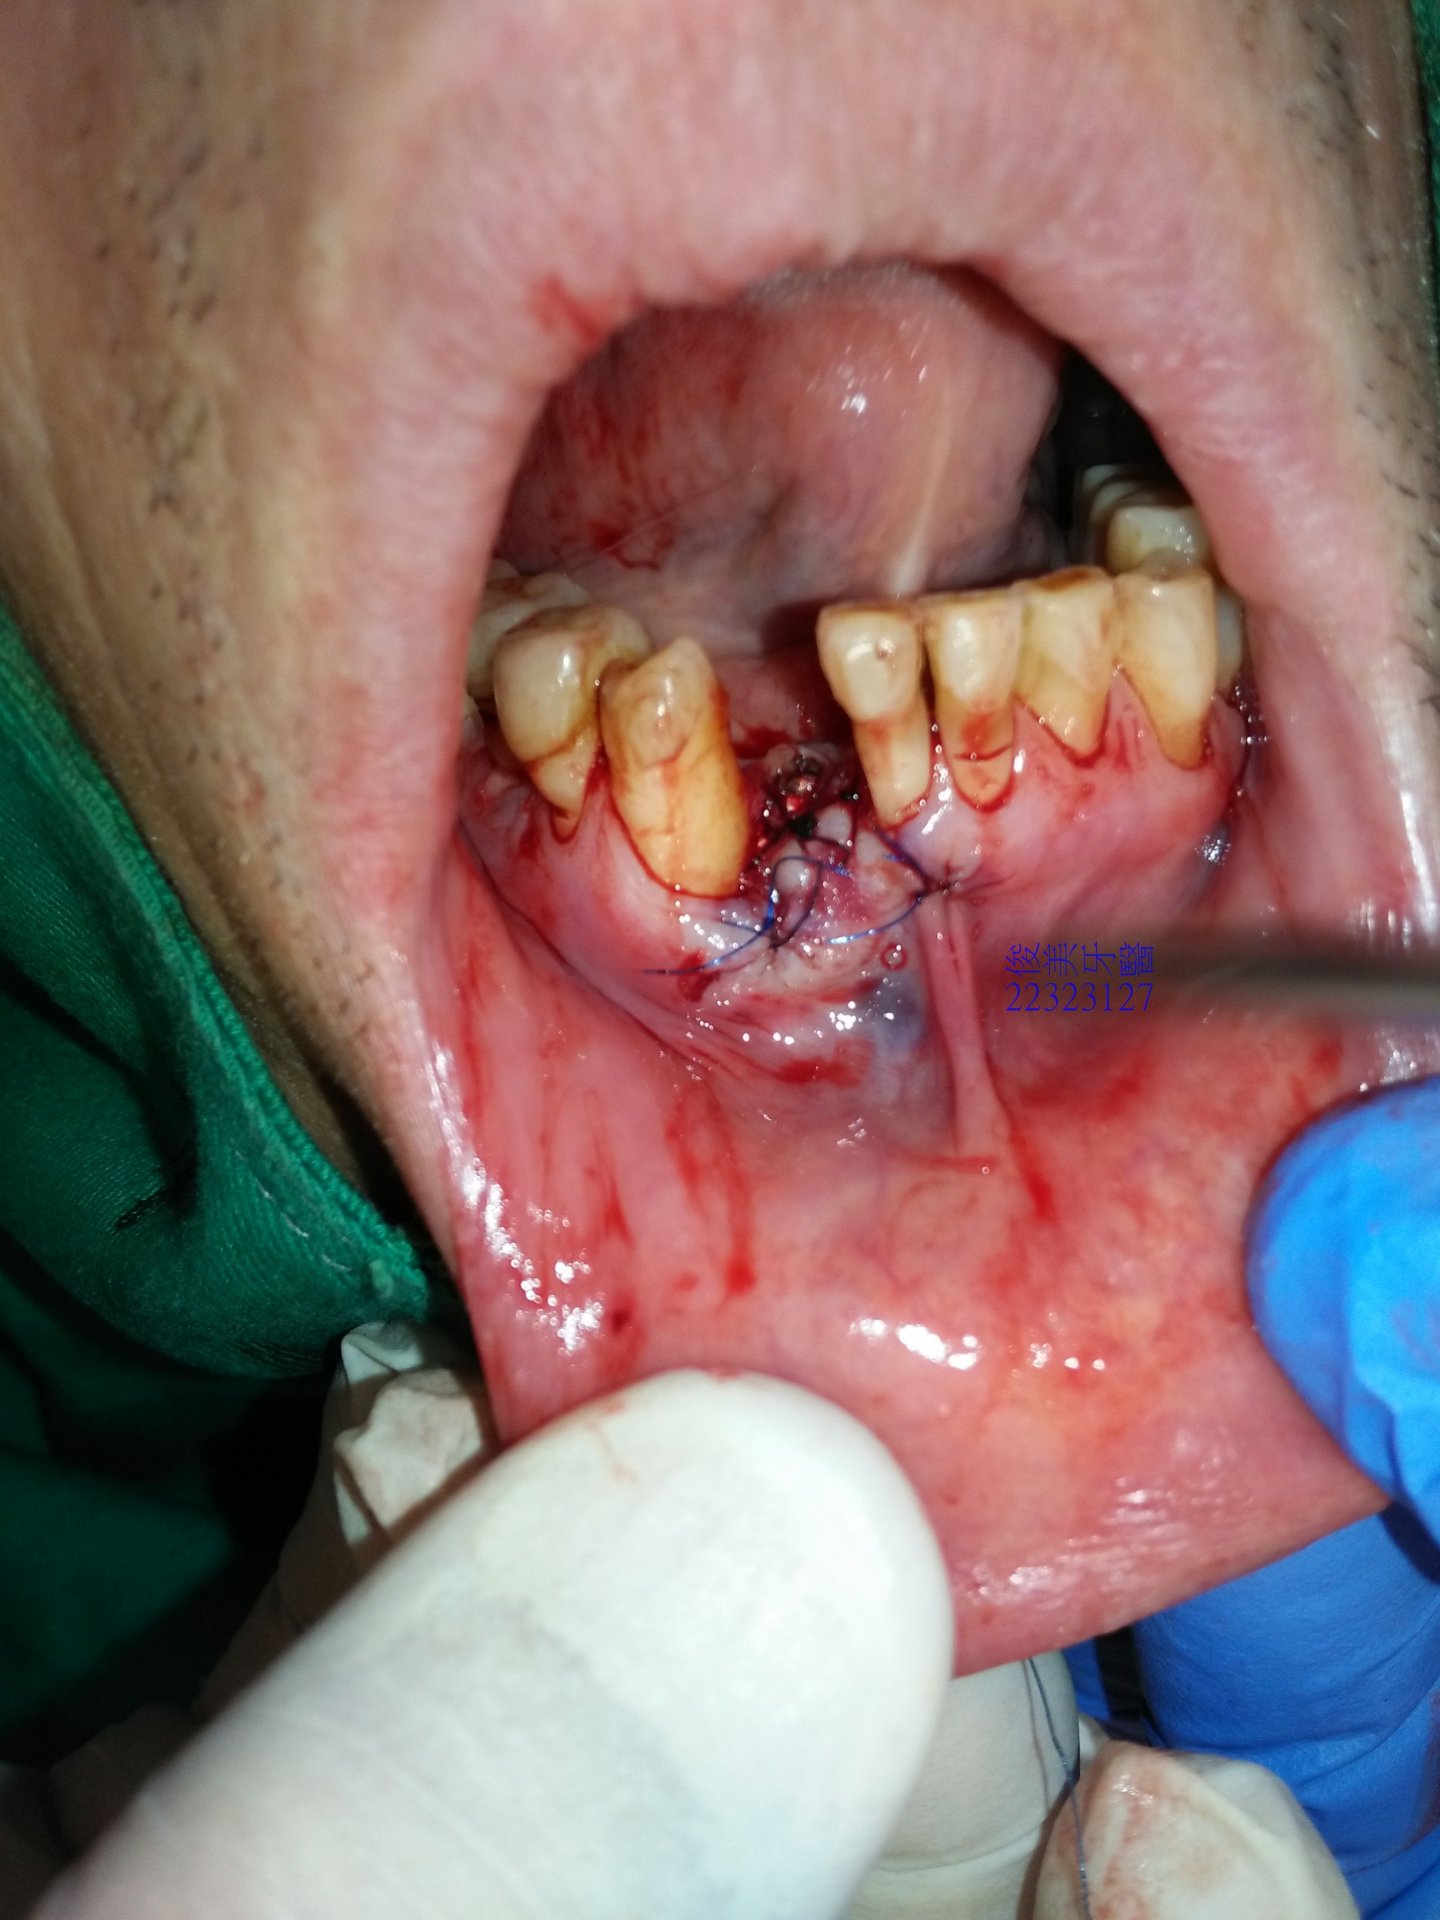

用皮瓣延長術將補骨區全部縫合,避免內部材料外漏。

並需患者強力冰敷 三天,避免傷口腫太大。